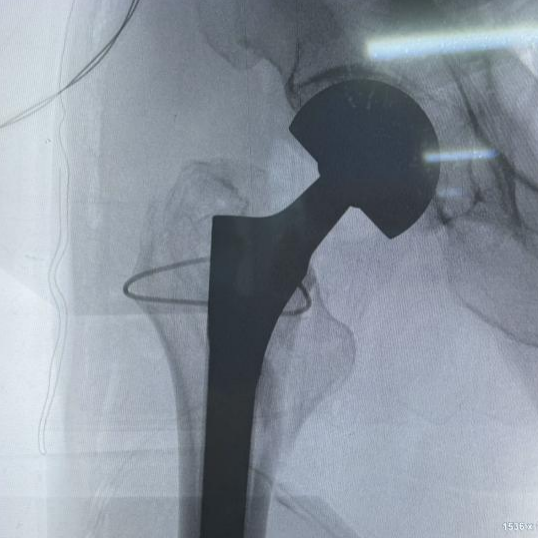

患者,男性,86歲,因不慎摔倒致右髖部疼痛、活動受限數(shù)小時入院。查體示右下肢外旋畸形,右髖部壓痛明顯,活動受限。X線片診斷為右側(cè)股骨轉(zhuǎn)子間骨折?;颊呒韧邪滩〔∈罚灰?guī)律服藥。經(jīng)多學(xué)科術(shù)前討論,綜合評估患者身體狀況后,決定行人工股骨頭置換術(shù)以迅速恢復(fù)髖關(guān)節(jié)功能,減少臥床時間,降低并發(fā)癥風(fēng)險?;颊咝g(shù)后第2天助步器輔助下逐步下床活動。

術(shù)前與術(shù)后影像學(xué)對比